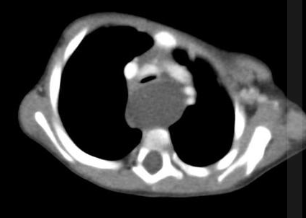

2 anos; masculino; respiração ruidosa desde o nascimento.

Cisto de duplicação esofágico

Predleção por meninos; diagnosticados na infância

Em geral assintomáticos; podem provocar estridor

Mais comuns no esôfago distal; geralmente não comunicam com a luz do esôfago;

TC: Cisto com densidade de líquido, margens bem definidas que podem realçar com contraste; podem complicar com hemorragia, infecção: nível liquido, espessamento parietal.